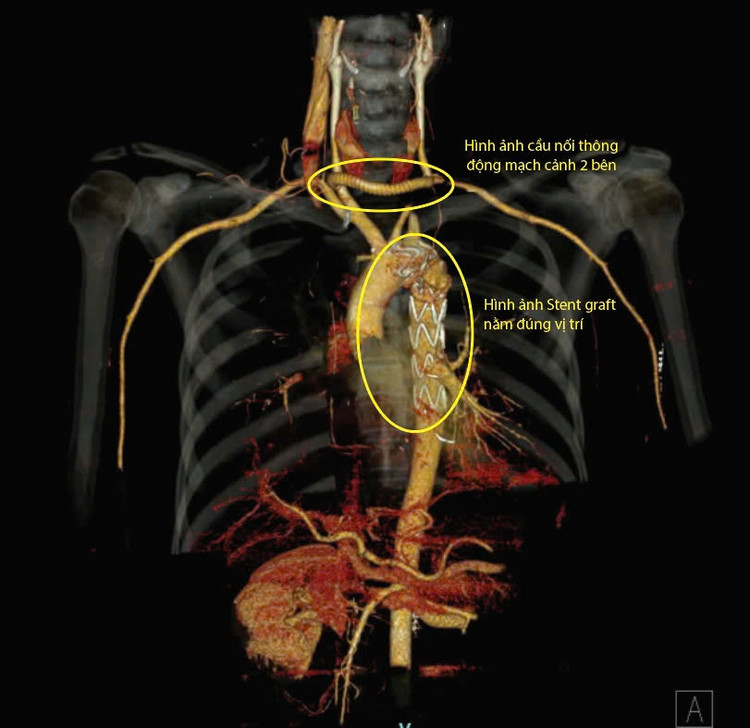

Toàn bộ quá trình phẫu thuật, đến can thiệp chỉ diễn ra trong khoảng 04 tiếng. Người bệnh điều trị hậu phẫu sau 08 ngày đã ổn định, không đau ngực, huyết áp và nhịp tim ổn định. Người bệnh đã được kiểm tra bằng chụp CT 128 dãy, vị trí đặt Stent Graft đúng, tưới máu tạng tốt và không có bất kỳ biến chứng nào có thể ra viện sau vài ngày tới.

| Hình ảnh động mạch chủ ngực sau khi được đặt Stent và hình ảnh cầu nối động mạch cảnh hai bên bằng mạch máu nhân tạo - Ảnh BVCC |